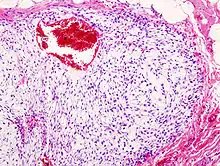

| Histopathologic image of chondrosarcoma of the chest wall. Surgical resection of recurrent mass. H & E stain. | |

Imaging studies – including radiographs ("x-rays"), computerized tomography (CT), and magnetic resonance imaging (MRI) – are often used to make a presumptive diagnosis of chondrosarcoma.[9] However, a definitive diagnosis depends on the identification of malignant cancer cells producing cartilage in a biopsy specimen that has been examined by a pathologist. In a few cases, usually of highly anaplastic tumors, immunohistochemistry (IHC) is required.